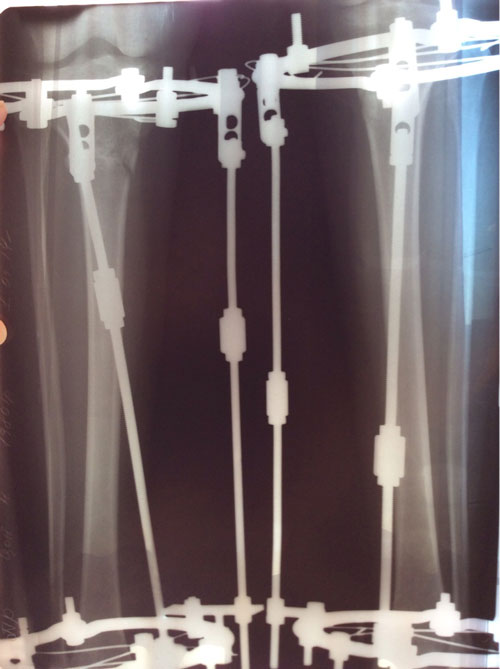

Дата операции 04.02.2014г.

Дата снятия аппаратов 05.05.2014г.

Срок лечения 89 дней.

Николь, ножки твои просто супер! Смотрела на них и восхищалась результатом! Поздравляю с окончанием аппаратного периода!